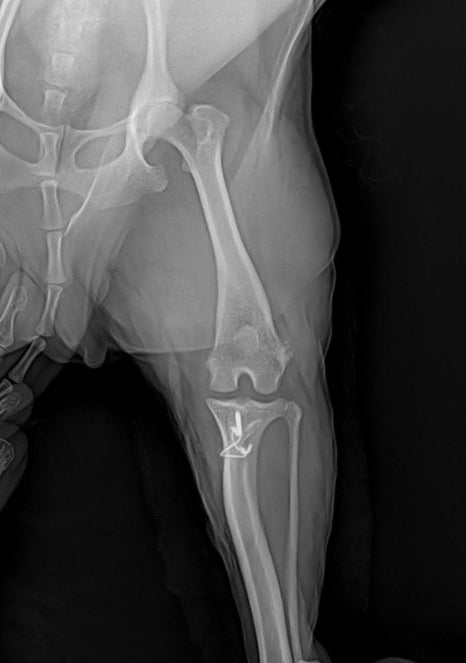

수술 및 회복 과정

슬개골수술 사진/ 출처: 라온동물메디컬센터

좌측 슬개골탈구 교정 수술은 계획에 따라 진행되었습니다. 무릎 정렬을 바로잡고 슬개골이 정상 위치에 안정적으로 유지되도록 교정했으며, 수술 과정은 특별한 합병증 없이 마무리되었습니다.

수술 후 방사선 사진/ 출처: 라온동물메디컬센터

수술 후에는 5일간 입원하며 통증 조절, 상처 관리, 초기 보행 재활을 병행했습니다. 과거 우측 수술 경험이 있어 보호자님께서도 회복 과정을 잘 이해하고 계셨고, 재활 협조도 매우 원활했습니다. 입원 기간 동안 점진적으로 체중 지지가 가능해졌고, 퇴원 시점에는 안정적인 보행이 확인되었습니다.